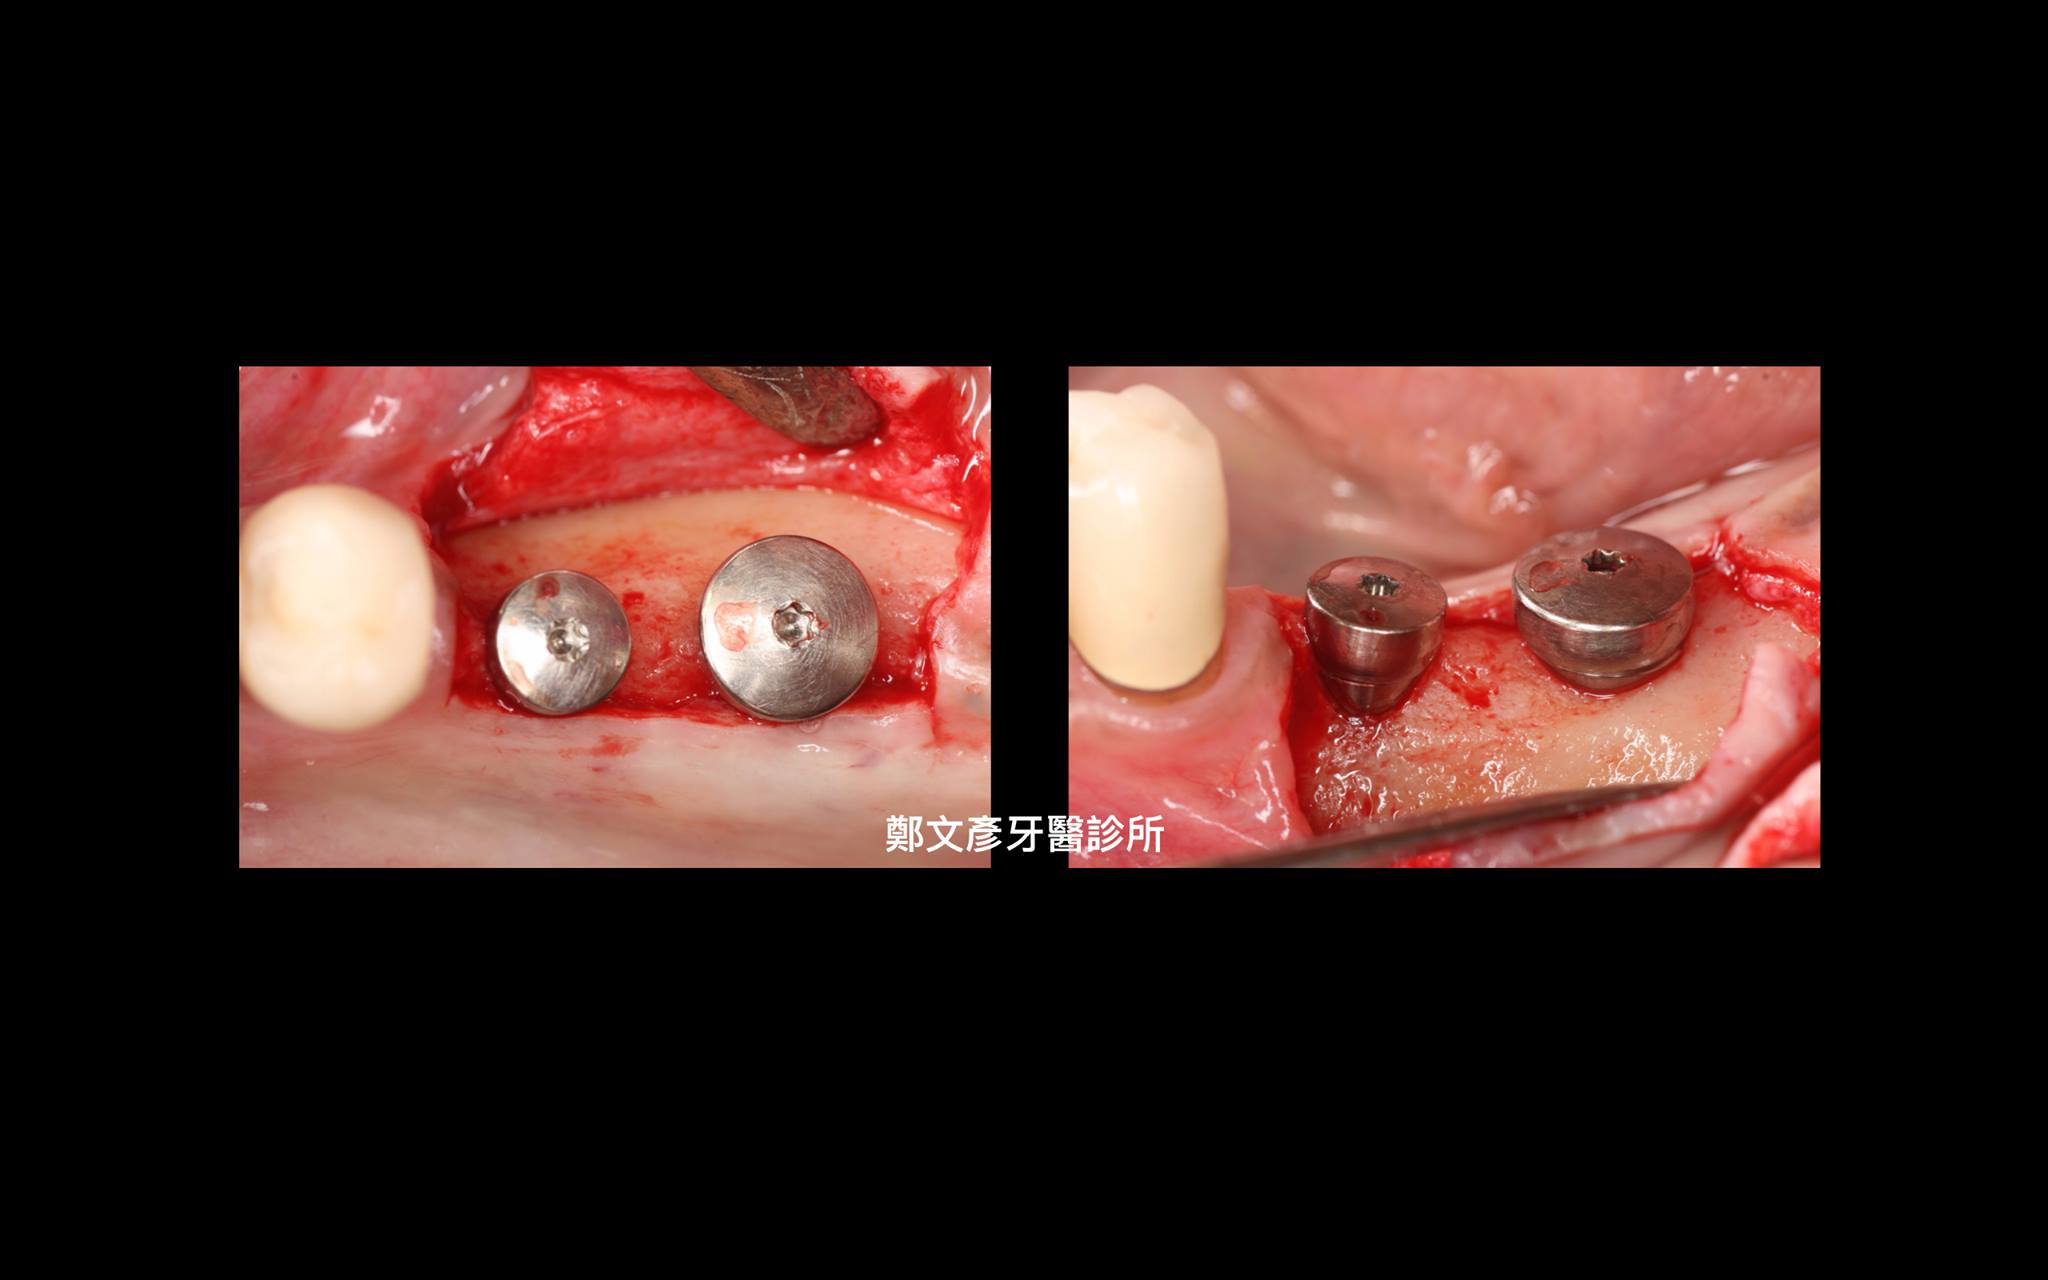

植牙美學(後牙區)

植牙美學